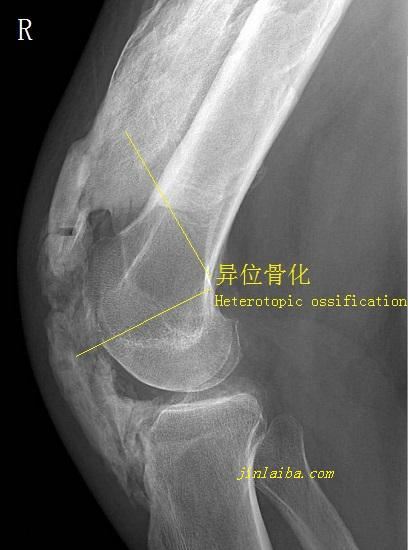

1、肘部局部感染。应在局部感染得到控制后再考虑实施网球肘手术治疗。2、肘关节僵硬。肘关节僵硬者,应先设法解决肘关节僵硬问题,否则即便实施清创术,运动功能障碍也不能解除。另外,肘关节处的手术易于引发软组织粘连及异位骨化,肘关节僵硬者更要谨慎。3、之前接受过肘部手术者。应充分考虑骨骼和软组织的愈合问题。

肘关节处的异位骨化